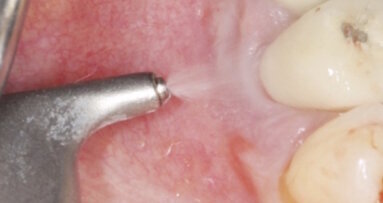

Meffert İmplant Enstitüsü Başkanı Dr. Ali Arif Özzeybek, implant tedavisinde yeni teknoloji ürünü özel frez ucuyla ...